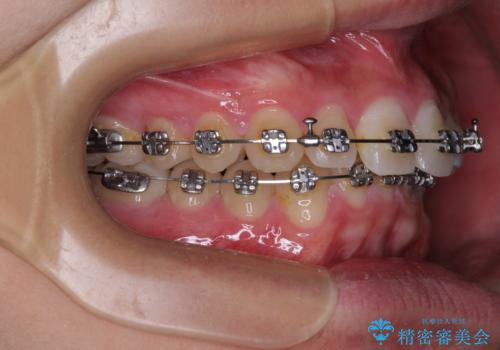

- メタルブラケット

- 1年1ヶ月

- 10-30回

ワイヤー矯正でもインビザライン矯正でも対応可能でしたが、インビザラインでの自己管理の煩わしさを避けるため、ワイヤー装置にて矯正治療を行うこととしました。